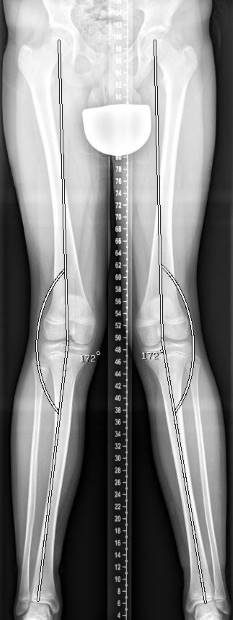

Die Mikulicz-Linie ist eine gedachte Linie vom Zentrum des Hüftkopfes bis zur Mitte des oberen Sprunggelenks. Orthopäden nutzen die Mikulicz-Linie zur Bestimmung der mechanischen Tragachse. Bei einer geraden Beinachse verläuft die Mikulicz-Linie durch die Mitte des Kniegelenks. Verläuft sie durch die Innenseite des Kniegelenks, handelt es sich um eine Varusfehlstellung (O-Bein). Bei einer Valgusfehlstellung (X-Bein) verläuft sie durch die Außenseite des Kniegelenks. Im Gegensatz zur anatomischen Achse, die durch die Knochen gebildet wird, bildet die Mikulicz-Linie die mechanische Achse. Besonders am Oberschenkel ist der Unterschied zwischen mechanischer und anatomischer Achse sehr groß.

In einer Röntgenaufnahme des gesamten Beines kann der Arzt das Ausmaß der Abweichung von der Mitte des Kniegelenks genau bestimmen. Der Wert wird als MAD (mechanische Achsdeviation) in Millimetern angegeben. Zusätzlich wird der exakte Winkel der Achsabweichung ausgemessen.

Bei einer höhergradigen Achsfehlstellung, die nicht mehr nur durch das Alter des Kindes erklärbar ist, wird eine beidseitige Ganzbeinaufnahme im Röntgen angefertigt. So kann der Orthopäde sekundäre Ursachen ausschließen. Anhand des Röntgenbildes führt der Arzt eine Achsbestimmung und Winkelmessung durch. So kann er das Ausmaß und die Lokalisation der Beinachsenfehlstellung genau beurteilen. Erneute Röntgenaufnahmen können den Verlauf einer Beinachsenfehlstellung kontrollieren.

Um die mechanische Achsdeviation (MAD), also das genaue Ausmaß der Abweichung von der Mitte des Kniegelenks abzuschätzen, ermittelt der Kniespezialist die Mikulicz-Linie. Diese bestimmt er anhand der Röntgen-Ganzbeinaufnahme. Sie führt vom Zentrum des Hüftkopfes bis zur Mitte des oberen Sprunggelenks. Verläuft die Mikulicz-Linie nicht mittig durch das Kniegelenk, sondern durch die Innenseite, handelt es sich um eine Varusfehlstellung (O-Bein). Verläuft sie durch die Außenseite des Kniegelenks, liegt eine Valgusfehlstellung (X-Bein) vor. Zusätzlich wird der exakte Winkel der Achsabweichung ausgemessen.

Zur Einschätzung der Beinachsenfehlstellung wird die Ganzbein-Röntgenaufnahme des Kniegelenks von vorne in 4 Quadranten eingeteilt. Verläuft die Mikulicz-Linie und somit die mechanische Beinachse innerhalb der beiden mittleren Quadranten, liegt eine normale bzw. geringgradig abweichende Beinachse vor, die nicht operativ korrigiert werden muss. Verläuft die Beinachse außerhalb der inneren Quadranten, liegt eine pathologische (krankhafte) Beinachse vor.